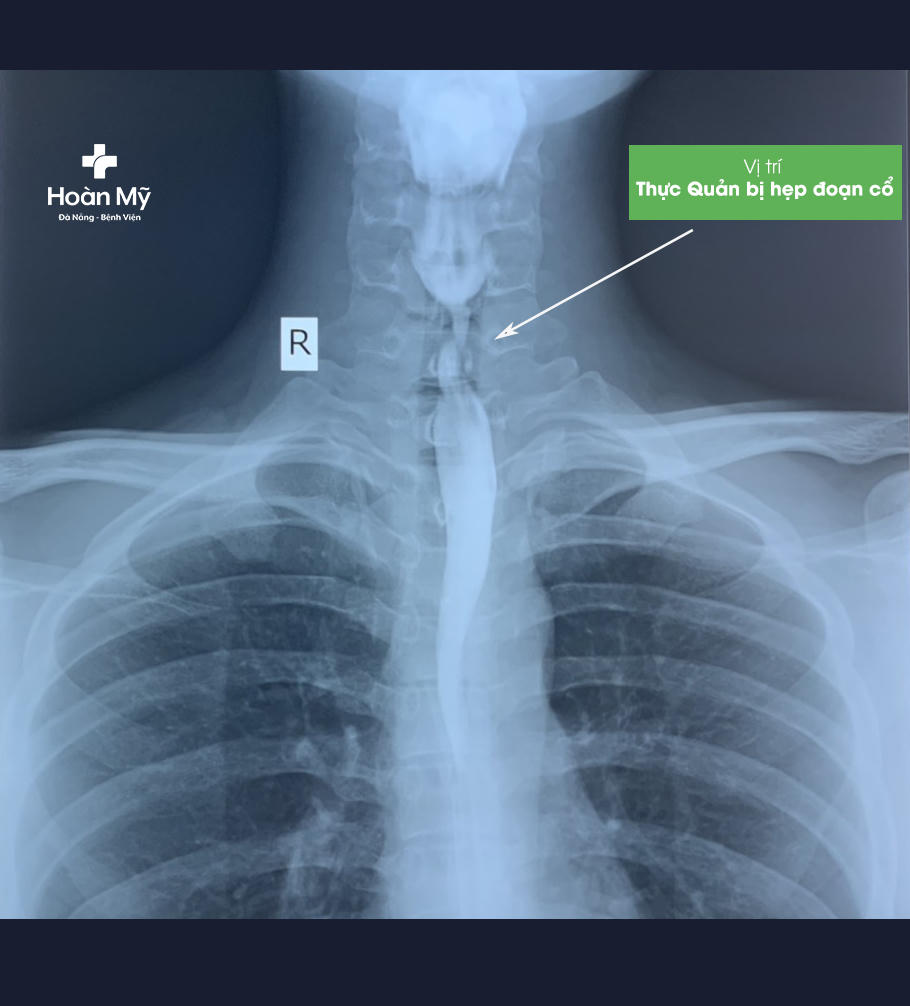

Bệnh nhân tên T.V.N (20 tuổi, Đà Nẵng) đến Bệnh viện Hoàn Mỹ Đà Nẵng thăm khám trong tình trạng nuốt khó, nuốt nghẹn, đặc biệt các thức ăn cứng. Qua kết quả nội soi dạ dày và chụp X-quang thực quản có cản quang cho thấy, anh N bị hẹp khít thực quản đoạn cổ, kéo dài một đoạn #20 mm.